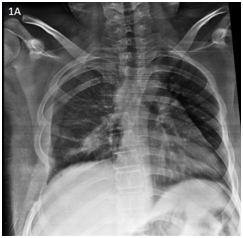

Two days after the in initial emergency room visit, the patient is admitted again with respiratory distress, fever and decreased oximetry by 88%. Because of the acute symptoms and clinical examination, pneumonia is suspected. IV antibiotic its initiated. Because previous the X-ray showed no other data, a computed tomography was performed, and pleural effusion was  confirmed with T4 listhesis (Figures 2-4).

<strong>Figure 2 </strong> Thorax CT scan Axial view. showing T4 listhesis (arrow). Right pleural effusion is observed.

Figure 2 Thorax CT scan Axial view. showing T4 listhesis (arrow). Right pleural effusion is observed.